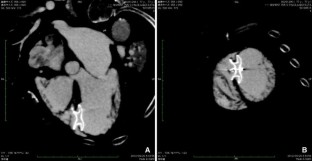

A 77-year-old woman underwent percutaneous closure of post-infarction ventricular septal defect. The defect was successfully closed with a 20-mm Amplatzer septal occluder with a small residual shunt and Qp/Qs improved from 3.38 to 1.48. She was discharged 30 days after procedure. To our knowledge, this is the first case reported in Japan.

Fig. 2